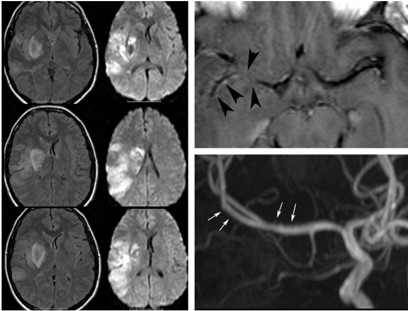

En primer lugar, se puede tratar el caso de los adictos al cannabis, cuya droga tiene efectos sobre el sistema endocannabinoide y en las áreas cerebrales vinculadas con la regulación de las emociones y el estrés. Un estudio de casos y control demostró mediante tomografía por emisión de positrones (PET) cómo la exposición crónica al cannabis, específicamente al THC, reduce la respuesta cerebral a la dopamina, y por ende, mayor puntuación de emocionalidad negativa en los adictos a esta sustancia respecto de los que no lo son. Esto se demostró con el uso de fármacos estimulantes, como el metilfenidato. Este mismo fenómeno también se ha observado con drogas como el alcohol, la cocaína y la nicotina. El cannabis también ocasiona una disminución en el metabolismo de la glucosa cerebral en el cuerpo estriado, tálamo y mesencéfalo(15) (ver Imagen 3).

En los casos de personas sin patología vascular subyacente, las hemorragias intraparenquimatosas se localizan con mayor frecuencia en los ganglios basales y el tálamo. Un caso como este se obtuvo en la literatura, correspondiente a una mujer de 23 años que sufrió una hemiplejía completa. Se le localizaron cantidades considerables de cocaína en el análisis de orina. La RM evidenció una isquemia en la rama MCA derecha con afectación de los ganglios basales(17) (ver Imagen 7).

Asimismo, la adicción a la heroína también genera afectaciones a nivel del SNC, provocando secuelas neurovasculares agudas y crónicas, como leucoencefalopatías, atrofia e infección. Las complicaciones agudas, como los ACV o la isquemia, suceden generalmente con la administración intravenosa de esta sustancia, que produce vasoespasmo, vasculitis y eventos embólicos.(22, 24) Se puede mencionar el caso de una mujer de 48 años con antecedentes de abuso de heroína, quien sufrió infarto agudo de divisoria de aguas con afectación de los lóbulos frontales y el justo caudal(24) (ver Imagen 17).

Entre el 5% y el 10% de las personas que tienen infartos asociados a la heroína se involucran globus pallidus o los ganglios basales. De igual forma, con la adicción a esta sustancia ocurren cambios isquémicos crónicos, a menudo son subclínicos, que se desarrollan a partir de estructuras microvasculares a largo plazo(24) (ver Imagen 18).

La leucoencefalopatía subaguda es un cuadro clínico que se genera con la administración de heroína precalentada inhalada. La sustancia se coloca sobre un papel aluminio, se calienta, y estos vapores emergentes son inhalados. Asimismo, esta sustancia genera cambios en la estructura cerebral, como el agrandamiento ventricular. Además, la droga provoca infecciones en el SNC secundarias a endocarditis por la inyección intravenosa de microorganismos, lo cual al mismo tiempo propicia complicaciones neurológicas, siendo el organismo más involucrado el Staphylococcus aureus.(22)

La endocarditis provoca infartos en el SNC debido a la oclusión de émbolos sépticos, aneurismas micóticos y en menor medida abscesos cerebrales(22) (ver Imagen 19). La heroína también provoca atrofias severas a nivel cerebral, como surcos y espacios subaracnoideos en los lóbulos frontal y temporal (ver Imagen 20).